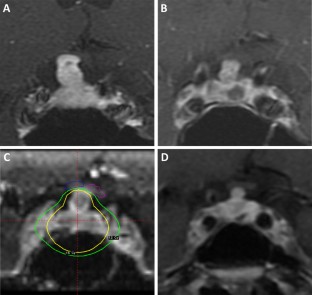

Five patients (four male, one female) having single-fraction SRS for persistent or recurrent SCO between 2002 and 2018. Median age was 56 (range 54–79) years. Pre-SRS treatments included transsphenoidal resection (TSR) (n = 3), multiple TSR (n = 1), and TSR, radiotherapy, and craniotomy (n = 1). Median target volume was 4.7 (range 1.8–8.4) cm3, with a median tumor margin dose of 17 (range 14–20) Gy. Median follow-up was 24 (range 10–69) months. All radiation-naïve patients achieved tumor control after SRS; tumor progression was noted 24 months after SRS in one patient who failed prior radiotherapy. No radiation-induced complications were observed after SRS. Systematic literature review of 43 cases in addition to the five cases presented here showed that tumor progression/recurrence was more frequent after STR compared to GTR (P < 0.001). Ten previous cases of radiotherapy for SCO have been reported, but most did not detail radiation volumes, doses, or outcomes.